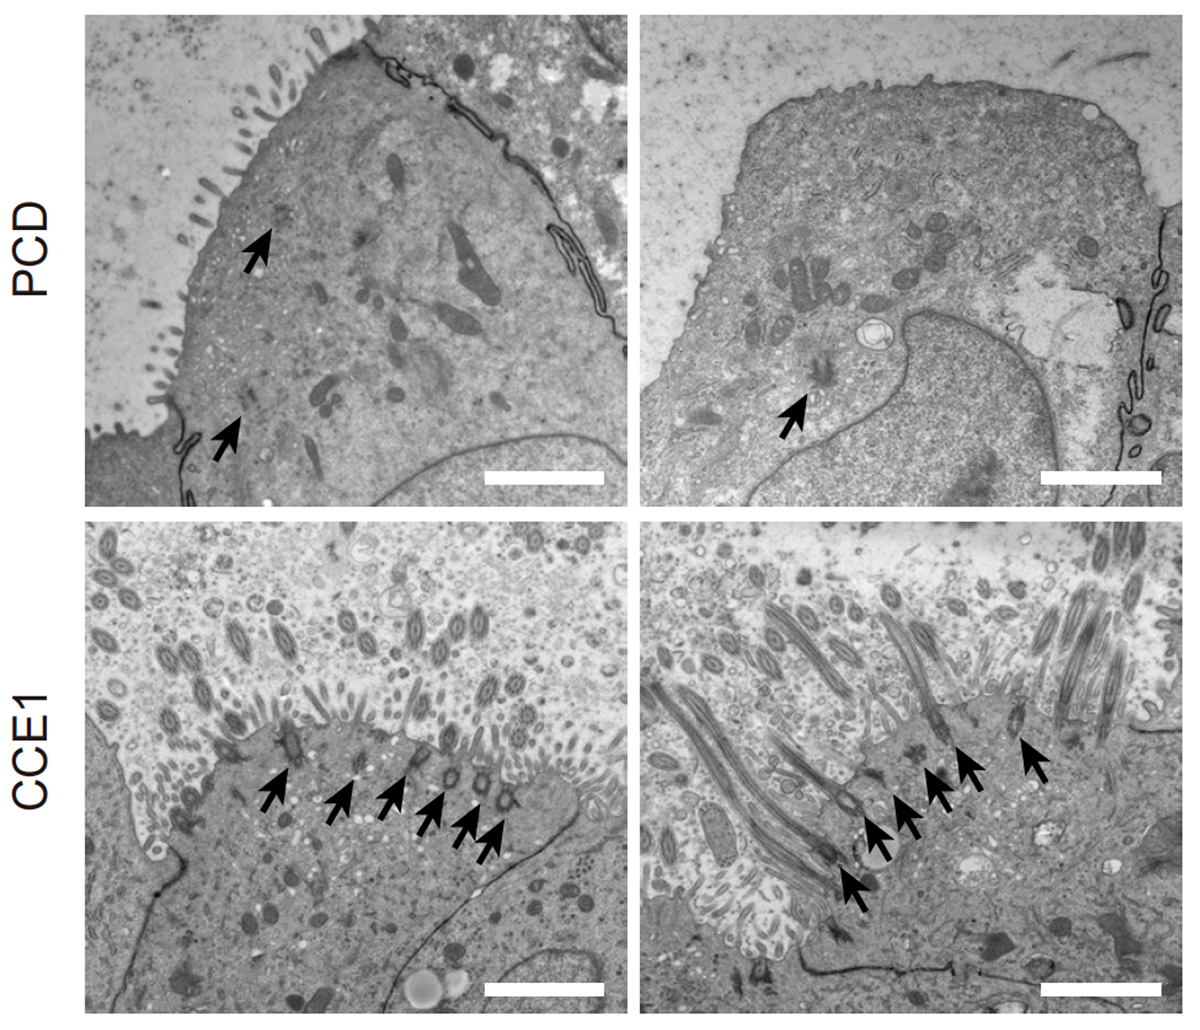

電子顕微鏡観察の結果、コントロールiPS細胞由来の気道上皮細胞(CCE1-iAEC)では正常な線毛と基底小体が形成されましたが、PCD患者さん由来iPS細胞から分化させた気道上皮細胞(PCD-iAEC)では線毛がほとんど存在せず、基底小体の形成も著しく阻害されていました(Fig. 2)。PCD-iAECでは、デューテロソーマル細胞の指標となるCD36陽性細胞がほとんど検出されませんでした。また、CCNO 遺伝子に病的バリアントがあると、NEK2 やANLN、CDC20 といったデューテロソーム関連遺伝子の発現が低下することが判明しました。

Fig. 2 iPS細胞から作製した気道上皮細胞の電子顕微鏡画像(矢印:基底小体)

CCNOはヒトの多線毛形成において、デューテロソームを介した中心小体増幅に必須の役割を担っており、その機能不全がPCDにおける重篤な多線毛形成減少を引き起こす一因であることが確認されました。